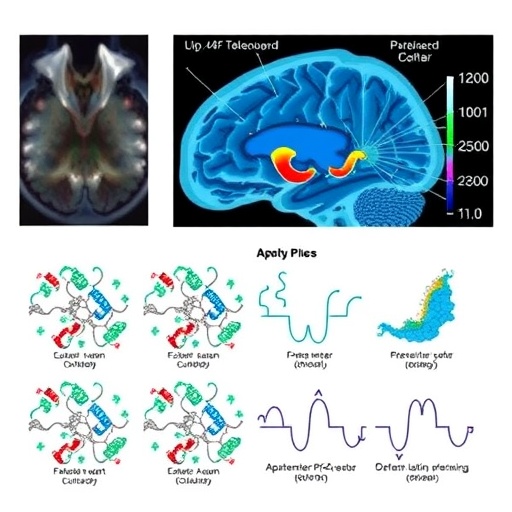

Enter aptamer-based proteomics—a technological breakthrough harnessing the specificity and sensitivity of aptamers, which are short, single-stranded oligonucleotides that bind proteins with extraordinary precision. Unlike conventional antibodies, aptamers are synthetically engineered, enabling them to target a broader array of proteins with remarkable stability and scalability. This technology facilitates the high-throughput quantification of thousands of proteins simultaneously, mapping the proteomic landscape in exceptional detail. The adoption of aptamer-based methods in pediatric TBI research offers a powerful new lens to understand how protein expression and interactions evolve after injury.

The study spearheaded by De Souza et al. embarks on an ambitious exploration of this proteomic frontier, enrolling pediatric patients with severe TBI and analyzing their plasma proteomes using an aptamer-based platform. Their approach is both comprehensive and nuanced, aiming to identify protein biomarkers that are not only elevated or suppressed following brain trauma but also functionally relevant to injury mechanisms such as inflammation, cell death, and tissue repair. These biomarkers have the potential to serve as early indicators of injury severity and predictors of long-term outcomes.

Critical to the success of this investigation is the study’s rigorous design, leveraging the high sensitivity of aptamer arrays to detect subtle protein expression changes that conventional assays might overlook. By profiling over a thousand proteins simultaneously, the researchers revealed distinctive signatures correlated with different stages and severities of TBI. This multiplex capability transforms proteomics from a mere inventory exercise into a predictive and dynamic tool, capable of guiding critical clinical decisions in real time.

Moreover, aptamer-based proteomics offers unparalleled reproducibility and affordability compared to mass spectrometry, positioning it as a highly scalable solution for clinical translation. Given the urgent need for point-of-care diagnostics in pediatric intensive care units, this technological innovation bridges the gap between bench discovery and bedside application. It also opens avenues for monitoring therapeutic responses and adapting interventions to individual molecular profiles, thereby ushering in the era of precision medicine in pediatric neurotrauma.